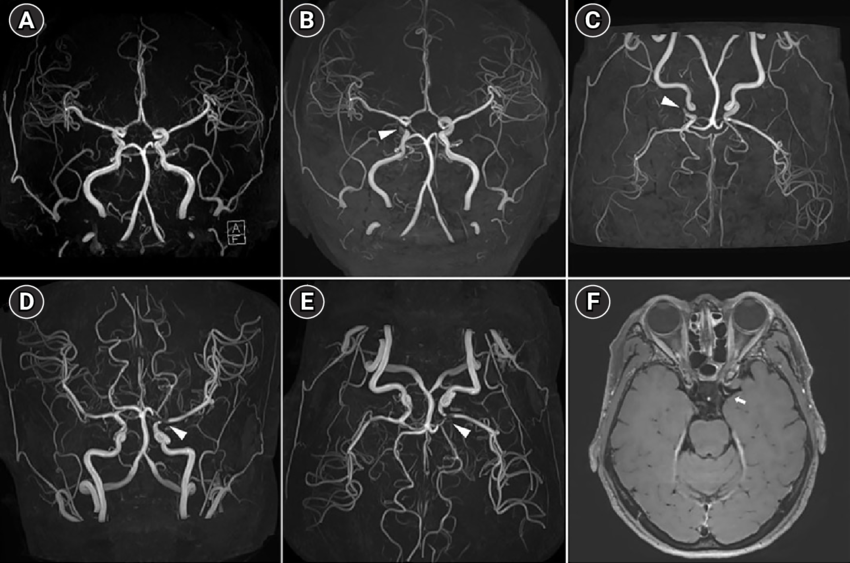

3D預測模型在 COSTA 資料集上,最終模型於61 筆測試影像達成 平均 Dice 0.8261 ± 0.0483,顯示分割穩定且具有泛化能力;從中片層對照可見主要動脈與多數分支均能被正確恢復,僅少數末端微細血管因訊號微弱或雜訊而出現斷裂。模型已具備穩定的血管辨識能力。

3D模型預測分析結果

下面展示為測試集其中三組案例的中間切片預測結果:

(左)輸入的 MRA 影像

(中)模型預測的分割結果(Prediction)

(右)對應的標註(Ground Truth)